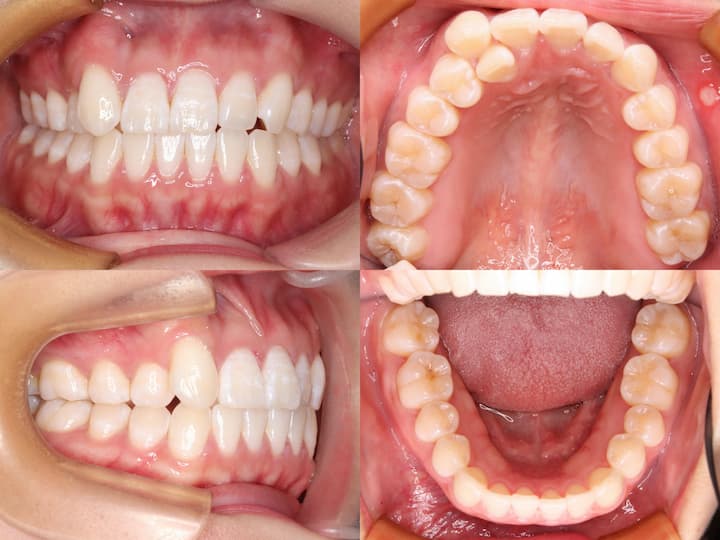

治療結果

上顎大臼歯の圧下により下顎骨のアンチクロックワイズローテーションが誘導され、口唇部の突出感は著明に改善されました。また、叢生も解消され、AngleⅠ級臼歯関係を維持したまま、機能的かつ審美的に優れた咬合状態を獲得することができました。

臼歯部の咬合も良好に保たれ、患者様からも高い満足度をいただいております。

本症例は、下顎骨の後方位を伴うハイアングル症例であり、口唇部の突出感が主訴の一つでした。このような症例では、上顎大臼歯の圧下による下顎骨のアンチクロックワイズローテーションが有効な治療戦略となります。

i-stationを用いた確実な固定源の確保と、フルサイズTMAワイヤーおよびパラタルバーによる緻密な咬合管理により、臼歯部のオープンバイトを生じることなく、大臼歯の圧下を達成することができました。

その結果、AngleⅠ級臼歯関係を維持しながら、口唇部の突出感を改善し、優れた治療結果を得ることができた症例です。